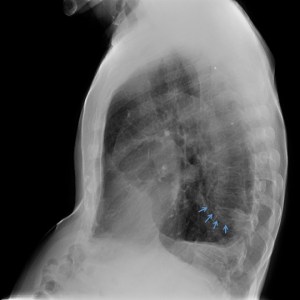

2- Engrosamiento con pinzamiento pleural postero basal izquierdo con imagen nodular de base pleural.

La imágen nodular, mejor visualizada en la placa lateral, ¿podría ser un proceso neoformativo? Pues podría, pero no lo es, estamos ante un caso de Atelectasia Redonda, se define así:

C- Signo de la cola de cometa: vasos convergiendo hacia la masa en modo curvilíneo, observar en placa y TC.

D- Otra característca es que la atelectasia redonda se suele observar bien en una sola proyección, a diferencia de la mayoría de nódulos (en nuestro caso, en AP no se obseva bien).

La atelectasia redonda es una lesión pulmonar muy poco conocida que ocasiona problemas de distinción con la neoplasia pulmonar. Es una lesión benigna, cualquier causa de inflamación pleural puede originar una AR, aunque se debe fundamentalmente a la exposición al amianto. La localización más frecuente es en los lóbulos inferiores y en el lado izquierdo. El signo de la cola de cometa corresponde a la retracción del tracto broncovascular por la atelectasia, es un elemento clave para identificar la AR. Recuerda: los vasos van convergiendo hacia la masa en modo curvilíneo.